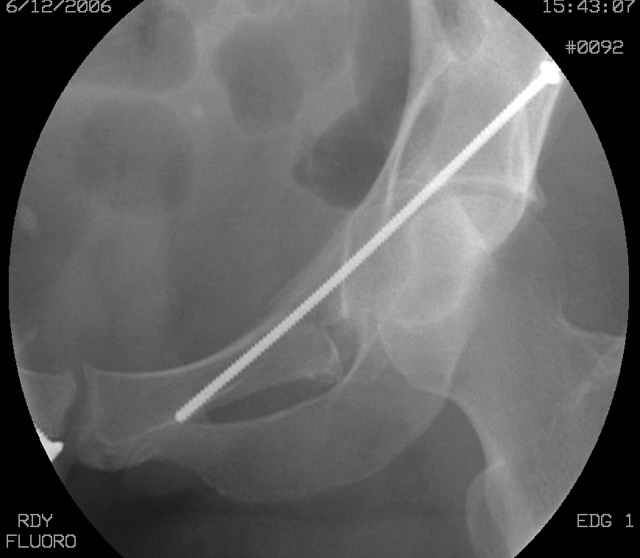

The 2nd example is of a motorcyclist with a transverse fracture-dislocation...he had a closed attempted reduction and placed in traction but the manipulative reduction was not concentric (not unusual for this injury pattern)...so the traction was adjusted to be just enough to disengage the head from the fracture (12#) until he could be cleared for surgery one day after injury...he was treated "urgently" then with a prone KL, clean the fracture, reduce and clamp it, screw it, support with a balanced plate, close, and enjoy...2-3hours, 400cc EBL, blah, blah, blah..

You can adjust the quadrilateral surface contact point as needed to get the fracture to reduce...we plan this based on the fracture orientation on the preop CT scan images...the clamp should be balanced to avoid over compressing one portion and distracting the other limb. Go back to and you¹ll see on the injury CT where the clamp tines need to be.

Here's a pic from the foot of the bed and you can see the clamp in the wound and the knee is extended so he must've had a tight rectus. The C-arm is rolled back to an obturator oblique image to reveal the anterior column...we put a slight outlet tilt to combine the images and give a better view of the anterior column...we can see the posterior column limb reduction in the wound, we can palpate the quadrilateral surface limb, and the image demonstrates the anterior column portion...you can adjust the tilt and rotation to image tangentially to the fracture plane if you'd like. We've inserted a 2mm K wire to site the starting point and aim/orientation for the drill and screw

Prone Imaging

OK, now we're inserting the drill percutaneosuy using a sleeve. This fluoro shot is not for this patient (notice no clamp) but I was too lazy to go searching the PACS for one with the clamp on, so pretend...I'll save the next ones and send along...the imaging is the same and the clamp doesn't obstruct imaging other than very rarely...you can always tilt the C-arm a bit to clear it if the clamp obstructs the exact spot that you'd like to see. We'll assume that everyone knows the safe zone for a medullary ramus screw. Use a calibrated drill and sleeve of known length to simplify your life...or use Alex's fancy cannulated screws...I like 3.5mm screws because the oscillating 2.5mm drill bounces and remains intraosseus when it oscillates and contacts endosteal cortical ramus... so will the screw, and like a long bent screw IF the fracture is clamped... if unclamped, when the screw contacts the endosteum, it pushes the reduction apart instead of bouncing. The big 7mm cannulated screws fit few patients and extrude...we very rarely use them any more...you'll see an old one later.

Screw insertion using the obturator-outlet combination image.